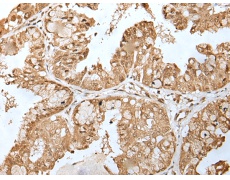

IHC positive control:

Human esophagus cancer and human liver cancer

IHC Recommend dilution:

25-100